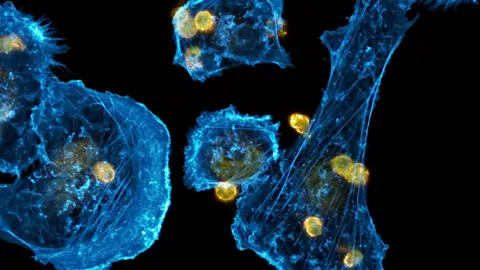

PA MediaLearning "how little" cancer patients often understood their diagnoses, Vincent wanted to create large-scale images of breast cancer cells, grown in a laboratory, being treated with a next-generation anti-cancer immunotherapy for an exhibition.

PA MediaInspired by Anais and other patients, Vincent had the idea to create large-scale images of breast cancer cells being treated with a next-generation anti-cancer immunotherapy to help educate those affected by the disease.

The images are of real breast cancer cells used in laboratory research, frozen in time and photographed using advanced fluorescent microscopy, before being artistically reworked by Vincent.

Vincent said: "By magnifying what is invisible to the human eye, it opens a window on a world that not many people have the chance to see.

"It's a world full of artistic shapes and unsuspected activity, where cells are growing, moving around, thriving, fighting each other, and eventually dying.

"It's a way of showing the beauty behind a very nasty disease."